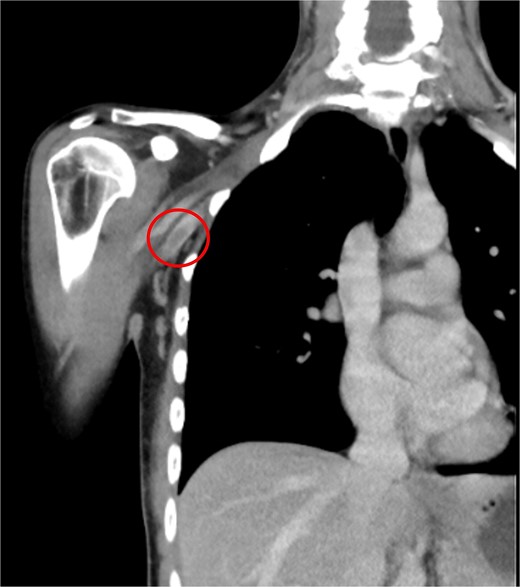

A 33-year-old woman with a history of oral contraceptive use and a BMI of 23.4 kg/m2 presented with breast hypoplasia. She was preoperatively evaluated and received an ASA I. A prepectoral augmentation mammoplasty was performed under general anesthesia. Même® MesmoMS® (Polytech Health & Aesthetics, Dieburg, Germany) 300-ml round implants were placed. The operative time was 80 minutes, and graduated compression stockings were used. On postoperative Day 7, the patient presented with pain, swelling, and erythema over the medial aspect of the right elbow and arm, with vital signs remaining normal. Doppler ultrasound revealed a right UEDVT (Fig. 2), and tomography showed thrombosis in the axillary and humeral veins (Fig. 3).

CT of the right upper extremity showing thrombosis of the right axillary and humeral veins (circle).